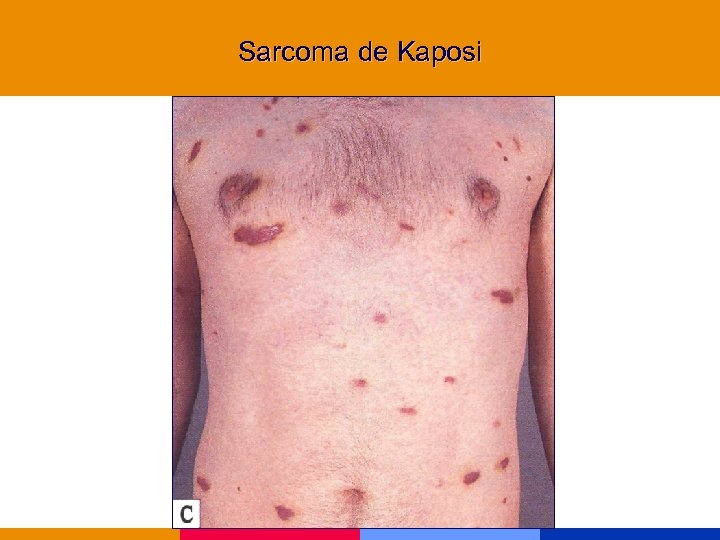

Sarcoma de Kaposi

Sarcoma de Kaposi

Sarcoma de Kaposi

Sarcoma de Kaposi

Sarcoma de Kaposi

Sarcoma de Kaposi

Sarcoma de Kaposi

Sarcoma de Kaposi